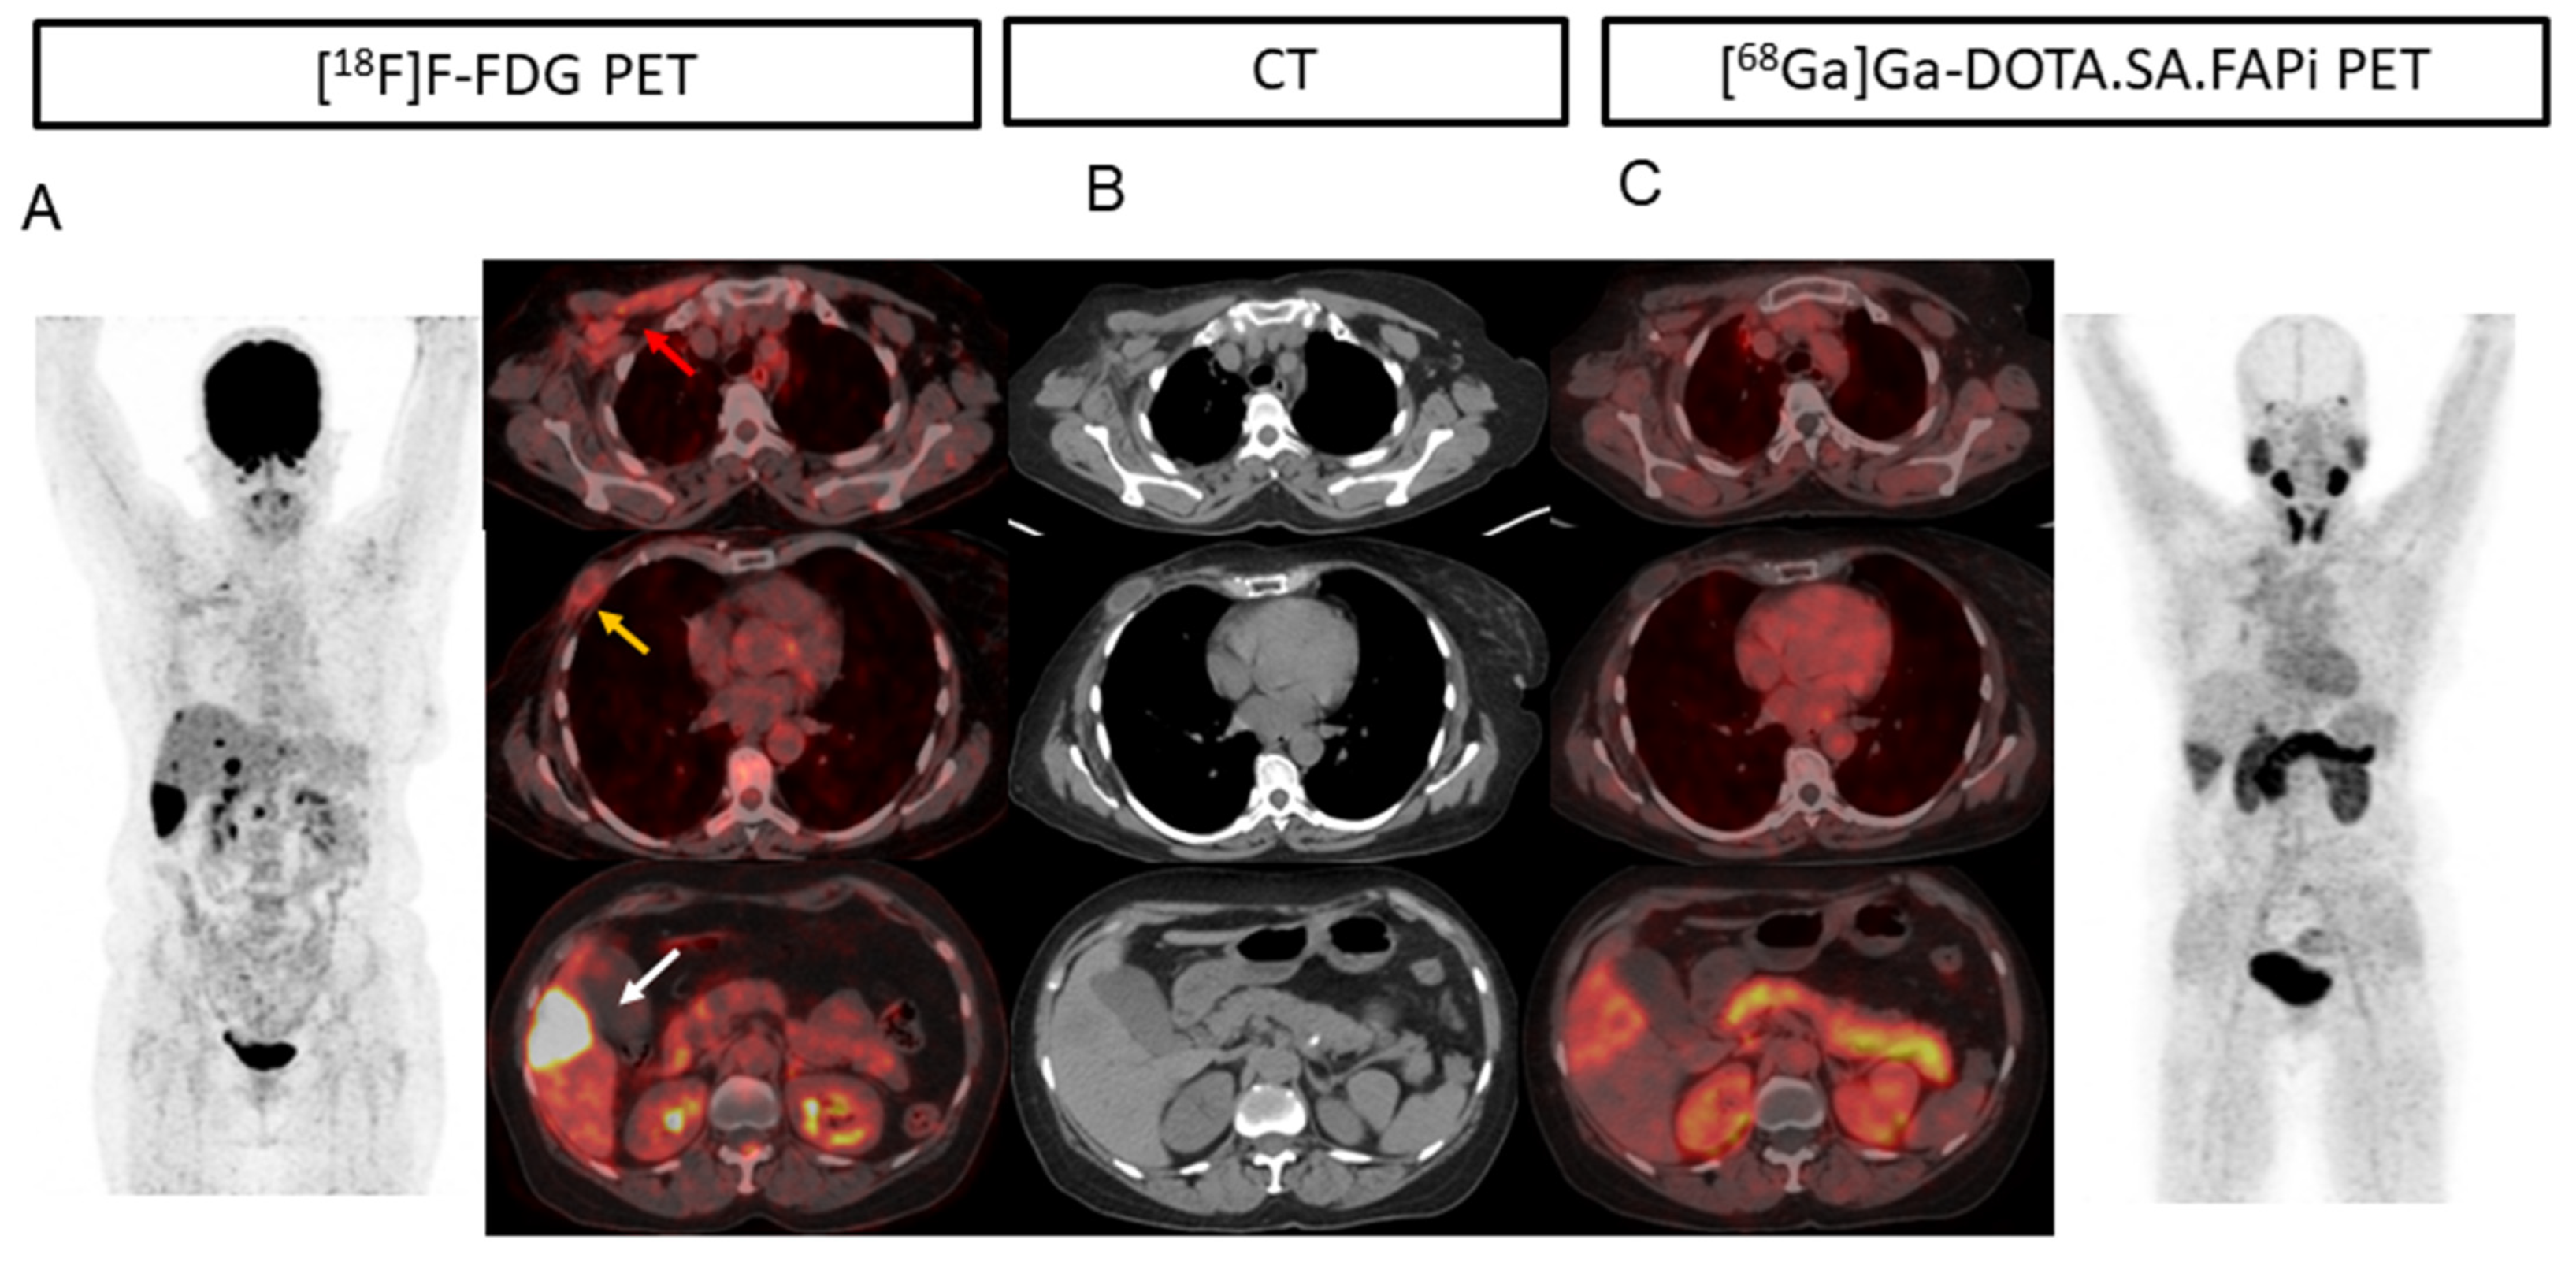

2. Results

2.3. Lesion-Based Analysis

2.4. Comparison of Uptake and TBRs in Tumor Lesions